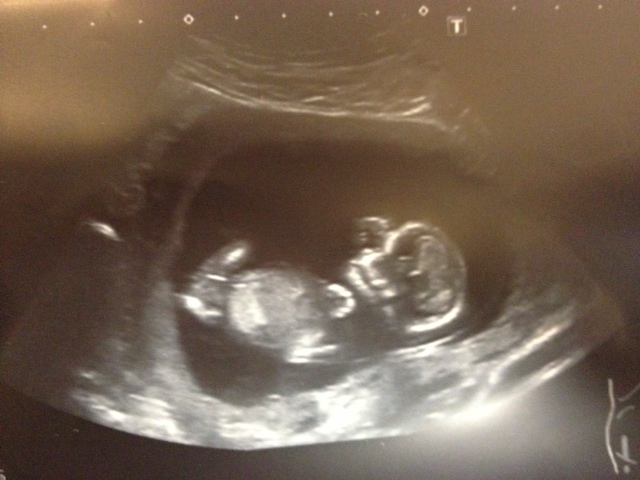

Any predictions? Attachment 7138

my gut says girl but i could be 100% wrong !!

Can't tell on this one...sorry

Girl